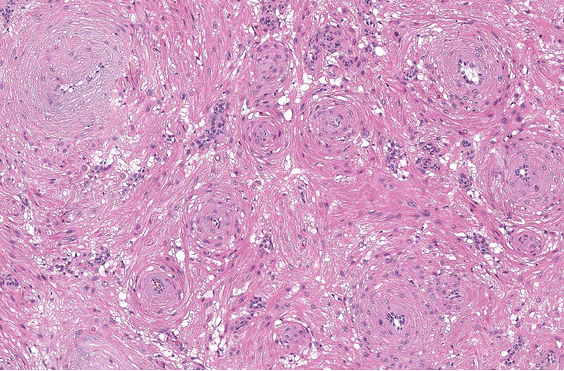

Low-grade fibromyxoid sarcoma

Low to moderately cellular, bland fusiform or spindled cells with focal to diffuse whirling in heavily collagenized stroma with abrupt transition to myxoid areas

45% have epithelioid areas

40% contain poorly formed but large collagen rosettes

Often infiltrates adjacent skeletal muscle

Occasionally has areas of increased cellularity, atypia, necrosis or mitotic activity characteristic of intermediate to high grade sarcoma

IHC: MUC4(+) highly sensitive (100%) and specific; CD99 (+)(90%) and BCL2(+) (90%)

CD34(-) c.f. intramuscular myxoma (which also MUC4(-))

Molecular: t(7;16)(q32-34;p11) FUS-CREB3L2 fusion in 90% or more

DDx: Intramuscular myxoma; myxofibrosarcoma (more pleomorphism/hyperchromasia and more developed vasc network); desmoid type fibromatosis (lacks myxoid areas); myxoid neurofibroma (wavy nuclei, thick collagen bundles in b/g)

px: requires long-term f/u as can metastasise years later

Image: abrupt transition to myxoid area